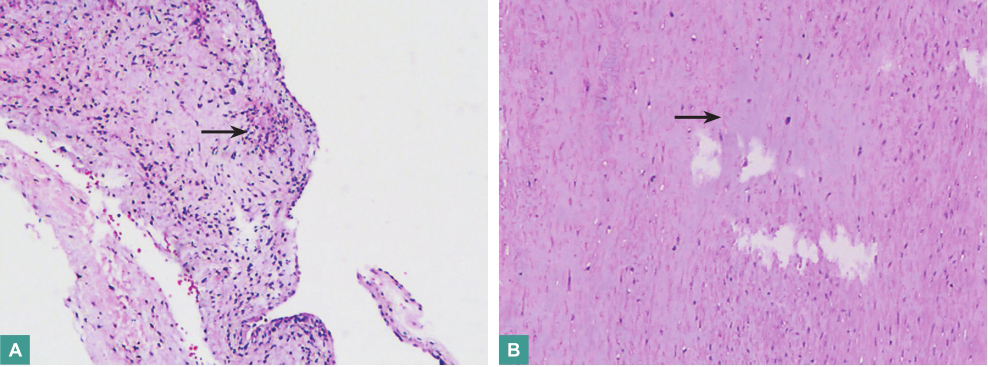

男性患者,31岁,以“反复胸闷、气促4年,再发7天”为主诉,于2015年5月入院。4年前,患者无明显诱因出现活动后胸闷、气促,无心悸、咳嗽、下肢水肿,以“马方综合征可能,心脏瓣膜病变”于心外科住院治疗,并于2011年9月13日行带主动脉瓣人工血管升主动脉替换术(Bentall术),术后病理示主动脉瓣及主动脉壁纤维组织增生,伴透明变性和黏液变性,间质少量慢性炎症细胞浸润(图1)。后患者分别于2012年10月和2013年11月因再次出现活动后胸闷、上一楼即感气短,两次就诊于我院心外科,均以“主动脉瓣周漏”行主动脉瓣膜修复+人工血管置入术,术后胸闷、气促短期内好转,但仍有反复加重。7天前,患者再次出现活动后胸闷、气促,并因术后不明原因主动脉瓣周漏及炎症指标升高,转入风湿免疫科进一步诊治。

图1 术后病理(HE染色;A.×100;B.×200)